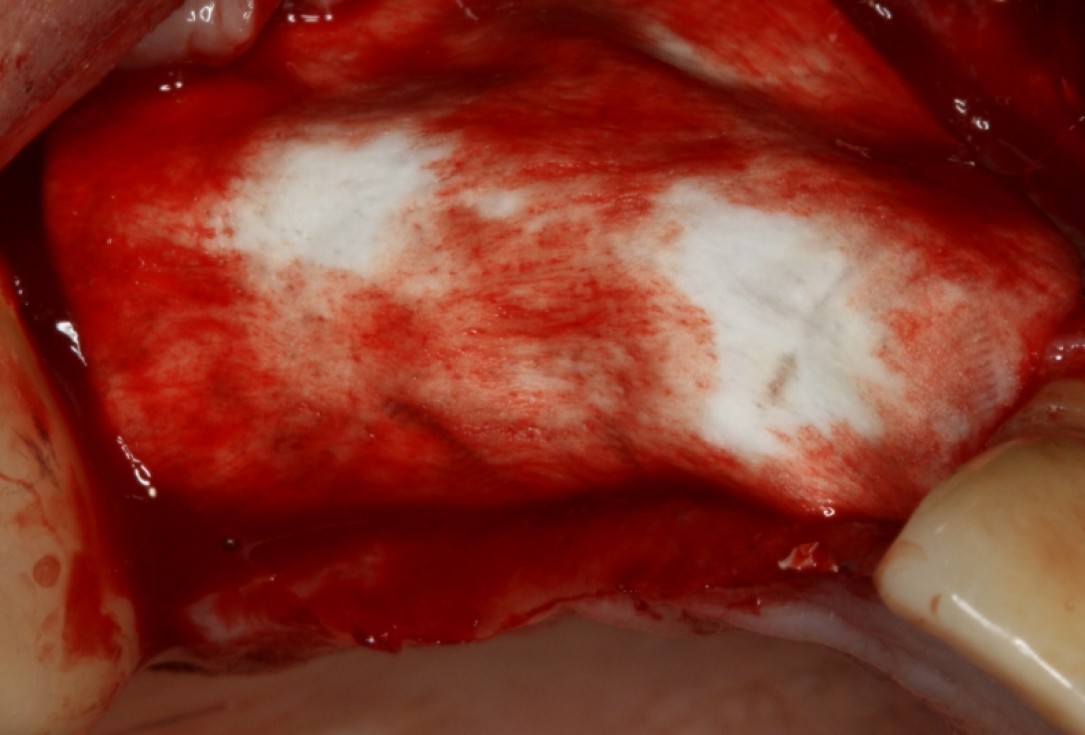

Three implants placed in a narrow posterior mandible